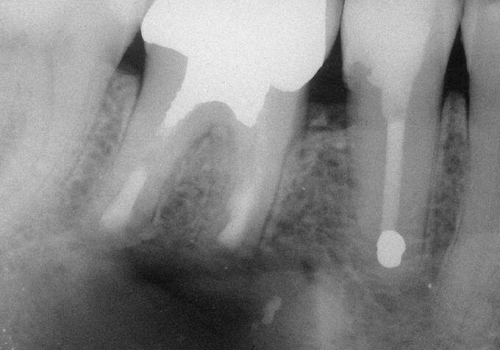

Endodontik müalicə (kanal müalicəsi) həyata keçirilən dişlərdə, kök kanallarının mürəkkəb konfiqurasiyası, yalnış və ya yetərsiz müalicə metodunun tətbiqi, bəzən də həkim səhvi/ehtiyatsızlığına bağlı olaraq təkrar iltihablanma – apikal ostit meydana çıxa bilir. Çox zaman bu tip iltihabi proseslər kliniki olaraq şikayətlərə səbəb olmadığından, zaman keçdikcə miqyasını genişləndirərək iltihab mənşəli odontogenik kistlərin yaranmasına gətirib çıxarır.

Bu zaman bəzi hallarda kanal müalicəsinin yenidən icrası (endodontik reviziya) mümkün olsa da, bir çox hallarda bu və ya digər səbəbdən həyata keçirilməsi mümkün olmur. Bu zaman əsas tətbiq edilən müalicə metodu dişi çəkməmək şərti ilə, iltihab ocağının uzaqlaşdırılmasını təmin edən – diş kökünün rezeksiyası metodudur. Bu əməliyyat vasitəsilə iltihab ocağı diş kökü ilə birlikdə kənarlaşdırılır və kök kanalları xüsusi metodla yenidən işlənir və doldurulur. Əməliyyat əsasən yerli ağrısızlaşdırma altında, xüsusi böyüdücü vasitənin tətbiqi ilə həyata keçirilir.